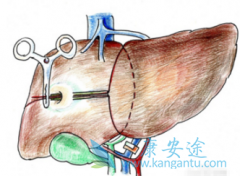

索拉非尼 (SORAFENIB)是晚期肝细胞癌(aHCC)的一线治疗。常规动脉化疗栓塞术(cTACE)是不可切除的肝癌的有效治疗方法。那索拉非尼治疗晚期肝癌是否需要联合TACE呢?既往的II期研究结果表明TACE联合索拉非尼(SOR+T)可改善预后。因此,J.-W. Park等 ...